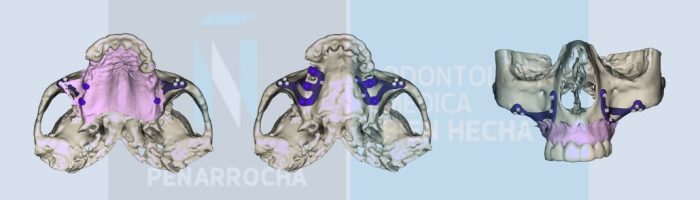

La cirugía ósea regenerativa e implantológica es otro tipo de cirugía bucal. Este tipo de cirugía se realiza cuando el paciente tiene atrofia ósea o falta de hueso, para posteriormente poder colocar implantes dentales.